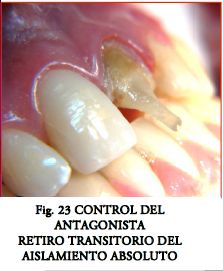

Con llaves de silicona, o con mucho cuidado si el caso así lo exige, quitando el aislamiento absoluto de manera transitoria se corrobora el espacio con el antagonista (fig. 23). El mismo es crucial en dientes delgados y permite ver el adecuado posicionamiento del poste en todos los sentidos.